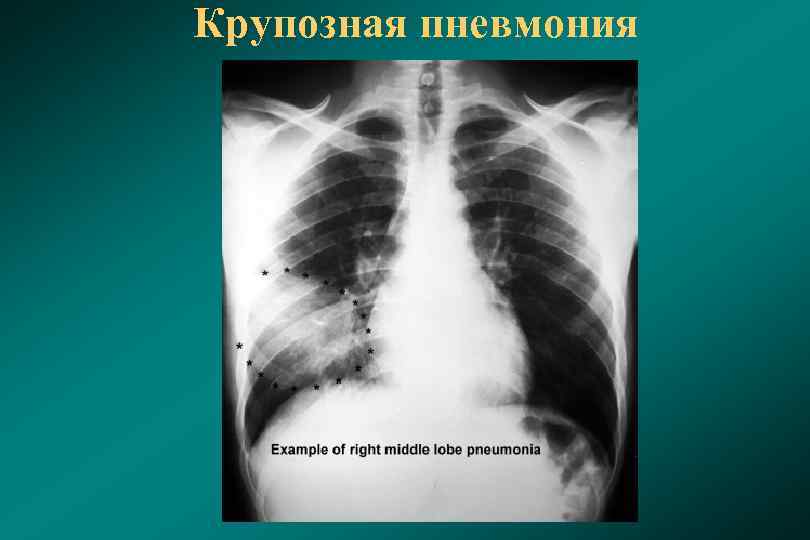

Медицинская тема: легочные осложнения при пневмонии